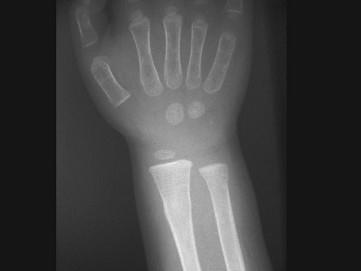

出生6个月的男婴,摔地后右手红肿,请结合CR片,选出骨折类型 ( )A、粉碎性骨折B、压缩骨折C、横行骨折D、斜行骨折E、青枝骨折

问题 出生6个月的男婴,摔地后右手红肿,请结合CR片,选出骨折类型 ( )

选项 A、粉碎性骨折 B、压缩骨折 C、横行骨折 D、斜行骨折 E、青枝骨折

答案 E